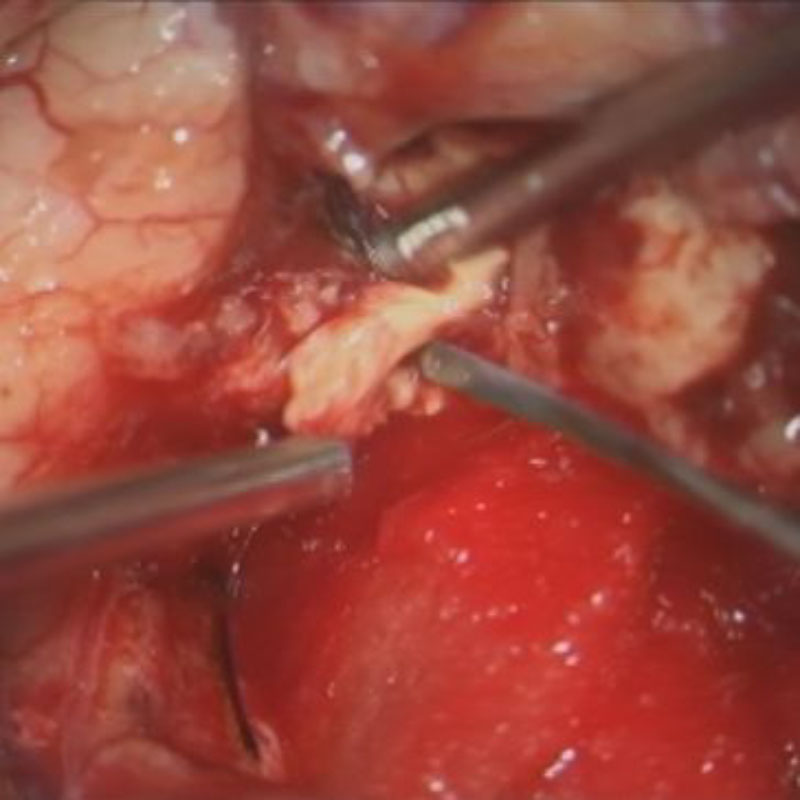

No.’25_26 摘出 前

No.’25_26  摘出 中